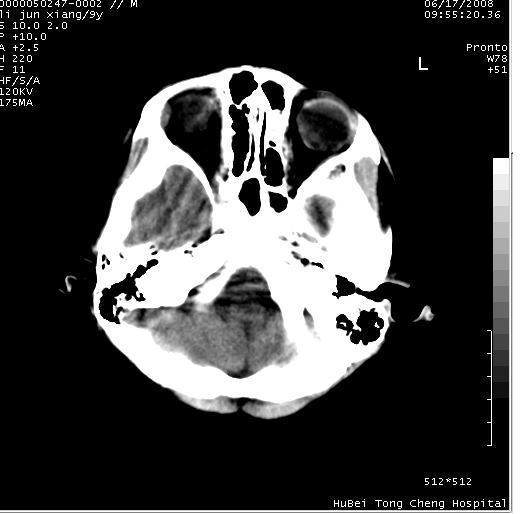

患儿 男,9岁。既往有“脑积水,脑萎缩?”病史(无影像检查资料),现无明显不适。其家长要求ct检查。

颅脑ct轴位平扫(层厚、层距均为10mm),图像如下: